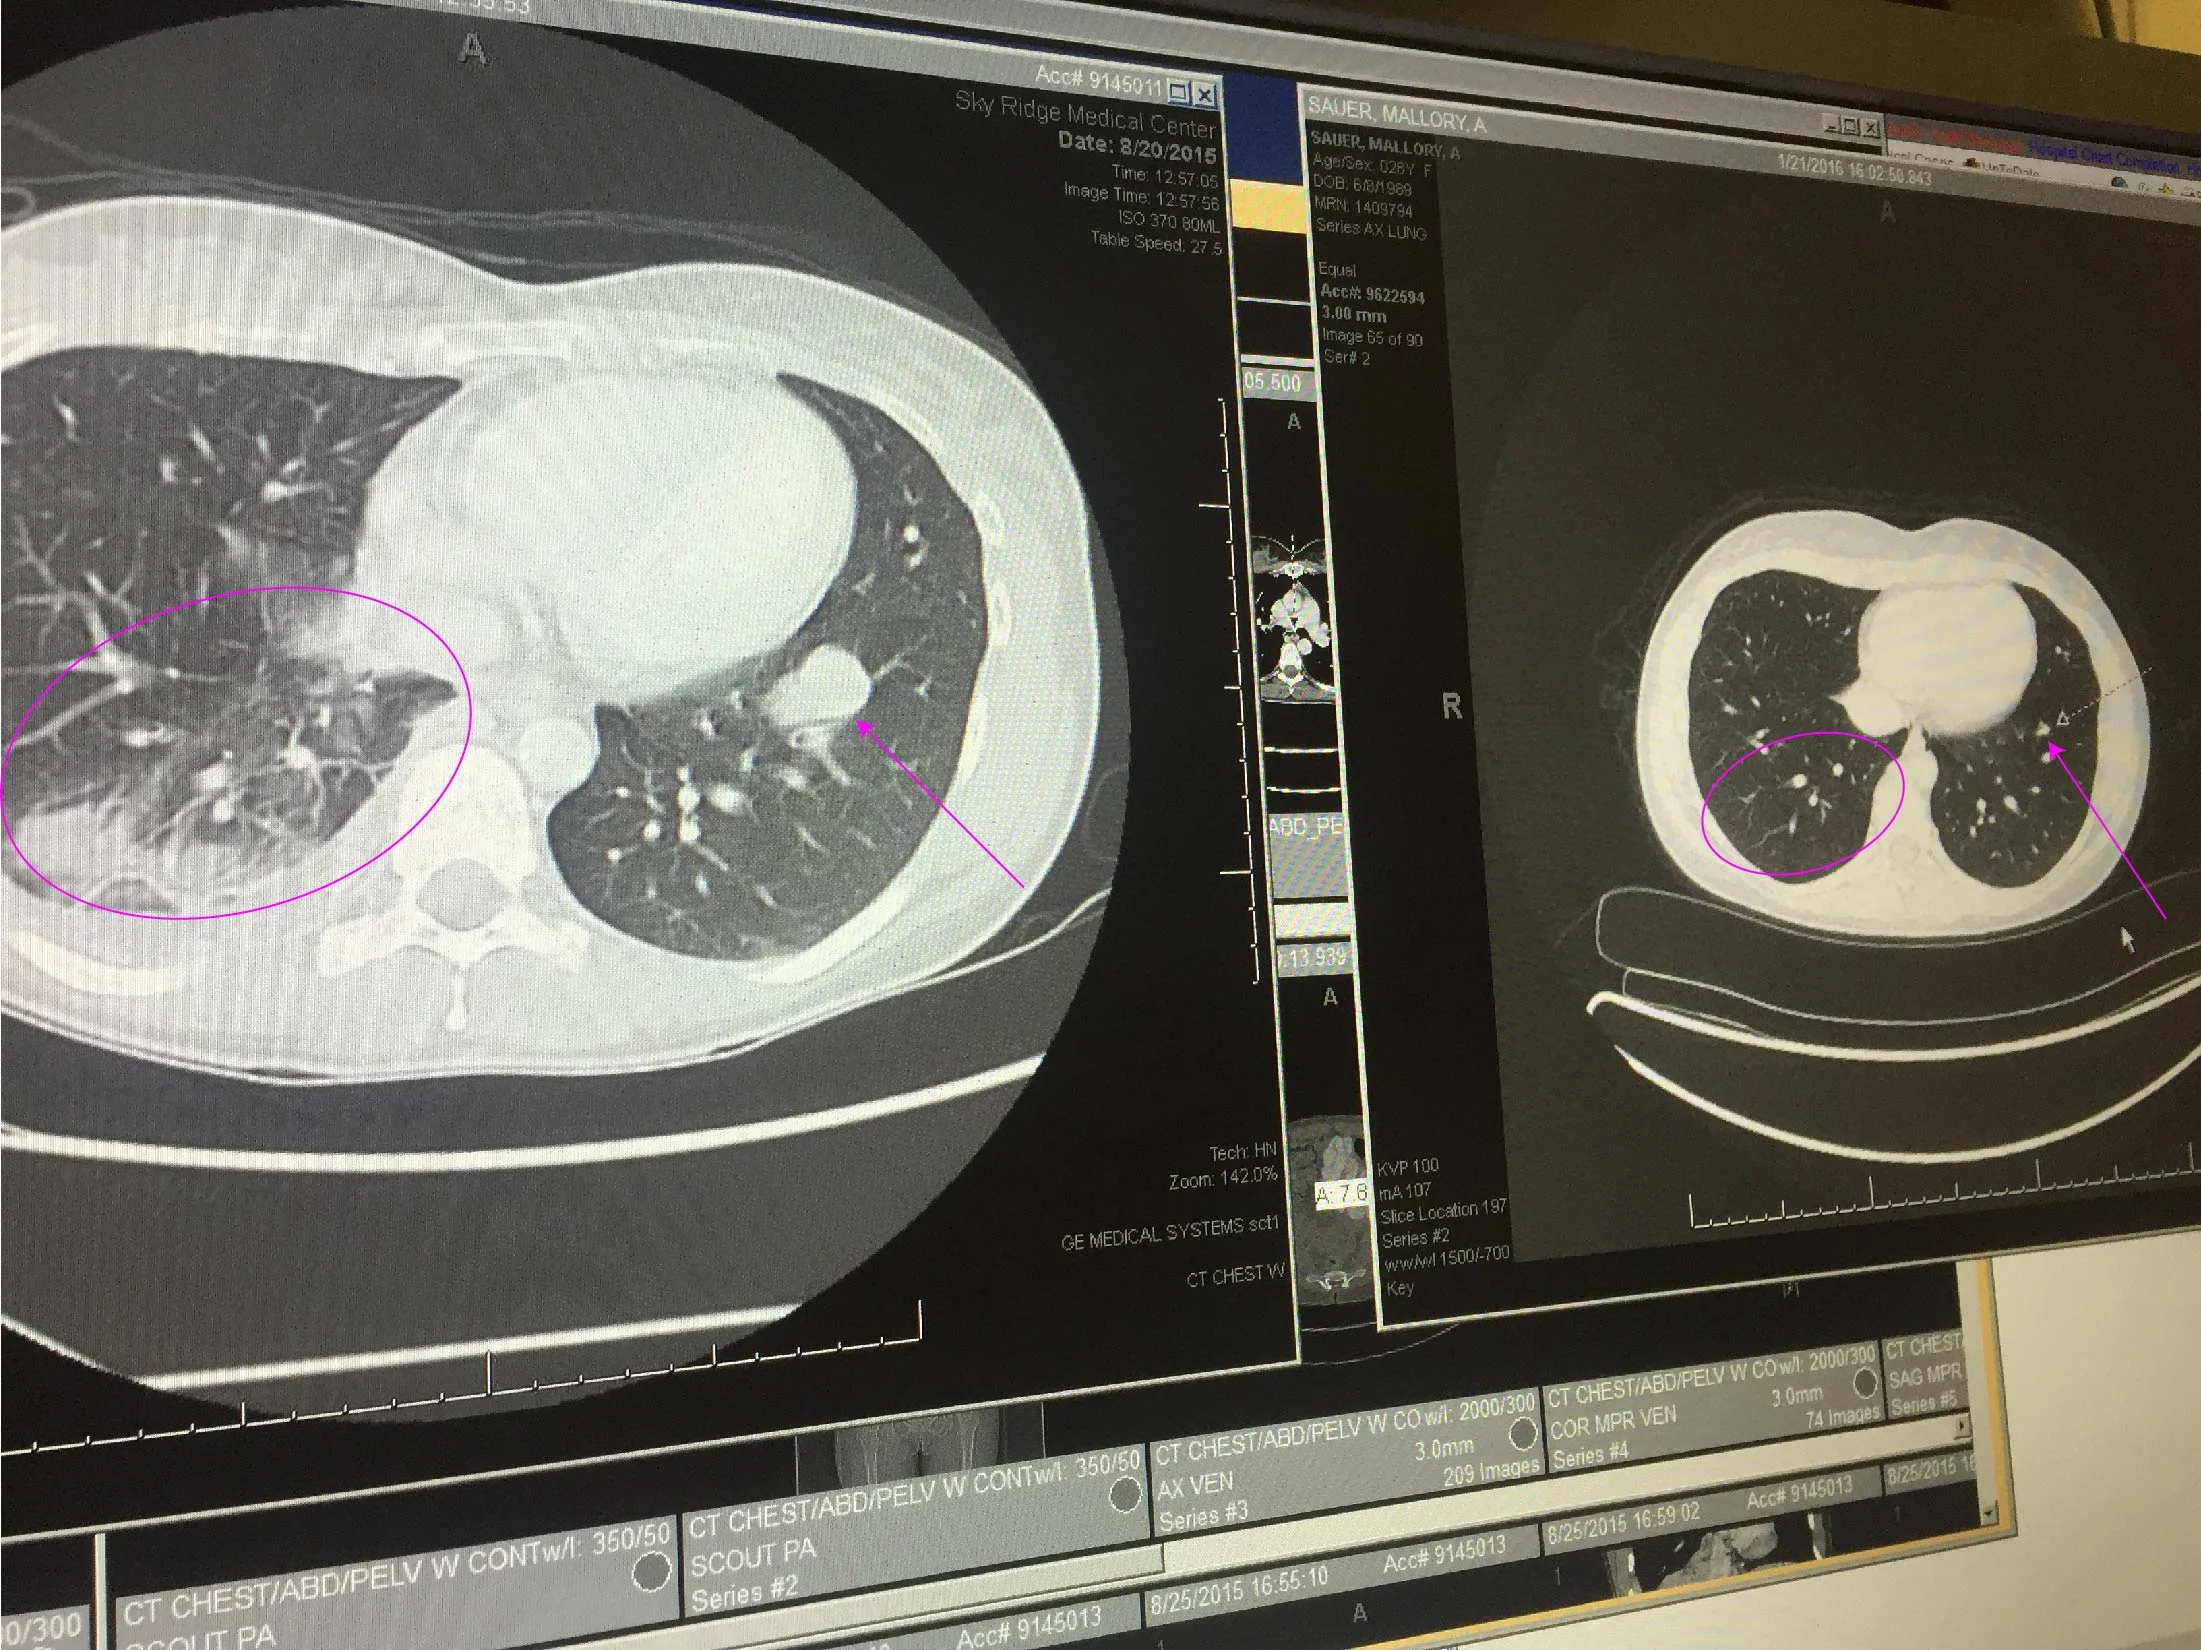

Good news, the tumors that are in my brain have not grown and no new tumors have developed. Bad news part 1, the melanoma in my lungs has come back and spread, meaning my body has started resisting the treatments I'm currently on. We're trying a new dosing approach to see if we can get my body to start responding again - fingers crossed that works. Unfortunately, the options for treating metastatic melanoma are extremely limited, and I'm already on the major treatments to fight this type of cancer. So, we flew out to UCLA and met with their melanoma specialist (he's world renowned and has access to studies and trials, etc. that my doctor here doesn't have full access to) and got a second opinion. There's one study that might be an option, but we won't know for sure yet for a little while longer. Also, this is just a study so there's no guarantee it would even work if I am eligible to participate. Bad news part 2, if I can't do the UCLA trial and my body continues to resist the treatment I'm currently on, my lifespan becomes measured in months and there's a chance I won't make it to the end of the year. I wish I could say that's just me being dramatic, but unfortunately those are words straight from two different doctor's mouths.